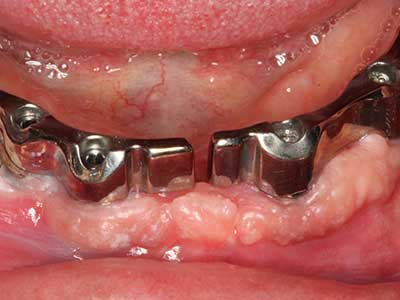

Indication: Bone splitting

Bone tissue is not simply a mineral structure but also contains a substantial proportion of collagen fibres. This means it not only has good compressive strength but also a degree of flexibility, which can be taken advantage of when performing bone augmentations. In the classical expansion procedure using bone splitting, the atrophied alveolar ridge is split longitudinally and carefully expanded after reaching an adequate osteotomy depth (Fig. 13-16), ideally without substantial removal of the periosteum (Brugnami, Caiazzo et al. 2014, Stricker, Fleiner et al. 2014). Screw and plate systems with increasing expansion distance have proven effective in separating the two bone lamellae while remaining below the fracture threshold. In general, residual bone widths of at least 3–4 mm are required (Chiapasco, Zaniboni et al. 2006) to guarantee adequate flexibility and sufficient bone coverage of the future implants. If necessary, a vertical relief osteotomy on one or both sides can improve flexibility. A combination with additional augmentation techniques, particularly on the buccal side, has been described as an alternative to the classical technique.

The splitting procedure is particularly atraumatic and there is no significant loss of dimension when using piezosaws, and there are no significant differences between implants in split jaws and implants in an alveolar ridge without a bone deficit (Chiapasco, Zaniboni et al. 2006, Danza, Guidi et al. 2009). However, sufficient continuous irrigation is essential, particularly with locally restricted and deep splitting to prevent thermal stress in the apical osteotomy regions.